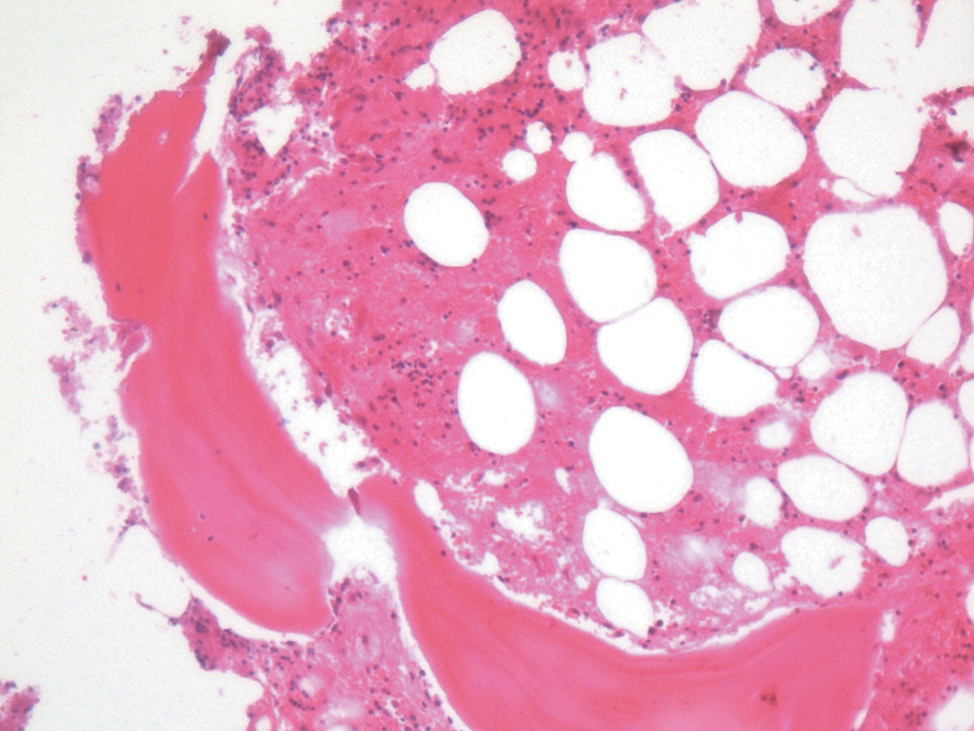

Кожа: акантоз, гиперкератоз, резкое утолщение рогового слоя, зернистый слой отсутствует, акантотические отростки широкие, ветвятся и соединяются между собой. Выраженная нейтрофильная инфильтрация с выраженными некротическими изменениями эпидермиса с формированием пузырей и отслойкой (рис. 1).

Рис. 1. Кожа. ×200, окраска гематоксилином и эозином. Акантоз, гиперкератоз, резкое утолщение рогового слоя. Зернистый слой отсутствует, акантотические отростки широкие, ветвятся и соединяются между собой

Fig. 1. Skin. ×200, stained with hematoxilin and eosin. Acanthosis, hyperkeratosis, and a substantial thickening of the stratum corneum. The figure demonstrates the absence of the granular layer. The acanthotic processes are wide, branching and connected to each other